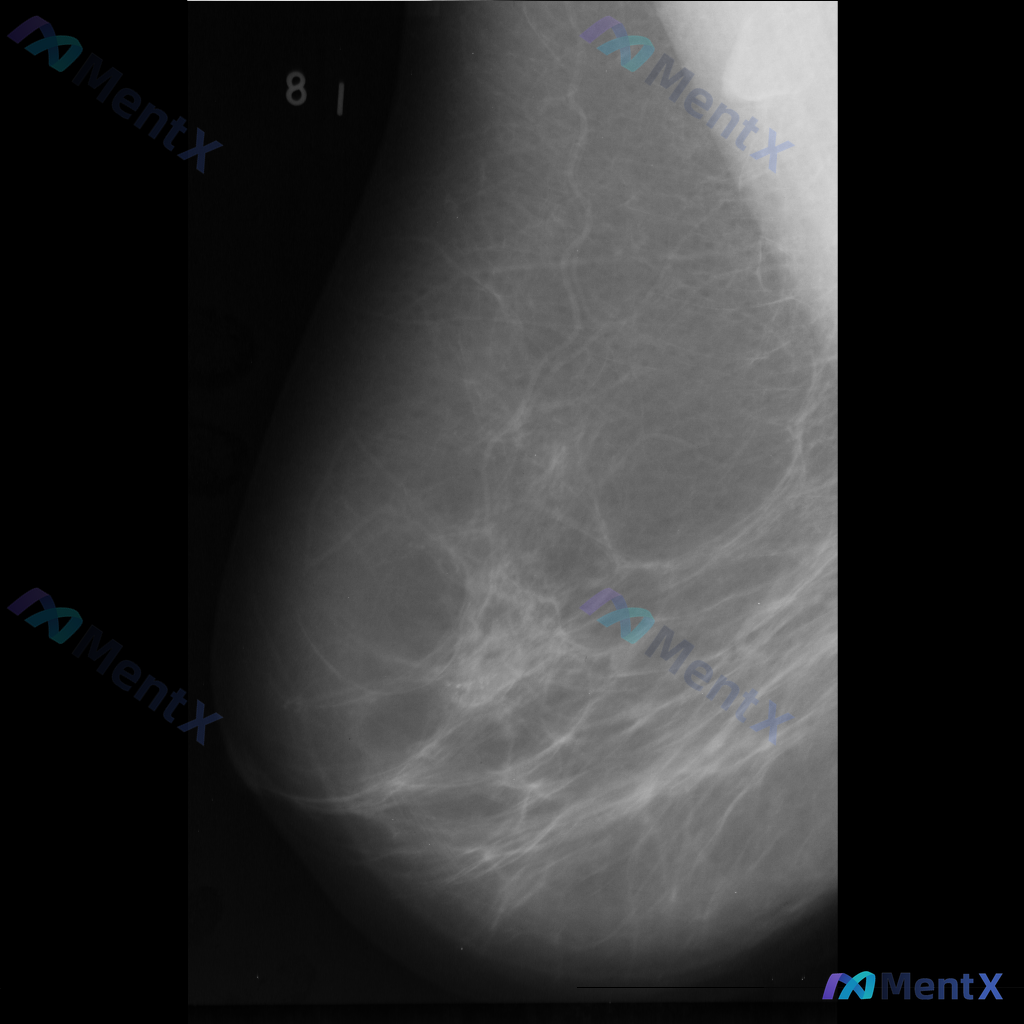

整理到一份乳腺钼靶影像资料,主要异常表现如下: - 部位:乳腺中部偏下方 - 影像征象:局灶性不规则腺体密度增高,伴结构扭曲 - 背景:致密型乳腺 目前仅单张影像资料,未提供其他体位、超声或临床病史。 想和大家讨论一下:单看这组异常表现,你会先往哪个方向考虑?后续如果要进一步明确,你觉得优先做什么检...

整理到一张乳腺钼靶影像的分析资料,大家可以先基于现有信息讨论一下。 基本影像学表现 - 可见形态不规则的致密区域,伴有结构扭曲和模糊边缘 - 背景乳腺腺体呈 BI-RADS B/C 型(致密性增加) 目前从影像上看,存在几种可能的方向,想听听大家的第一判断:单看这组影像学表现,你会先考虑哪一种异常方...